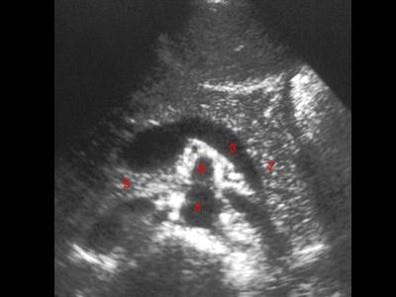

图示5所指部位?(?)A.脾静脉B.腹主动脉C.胰头D.下腔静脉E.肠系膜上静脉

问题 图示5所指部位?(?)

选项 A.脾静脉 B.腹主动脉 C.胰头 D.下腔静脉 E.肠系膜上静脉

答案 C